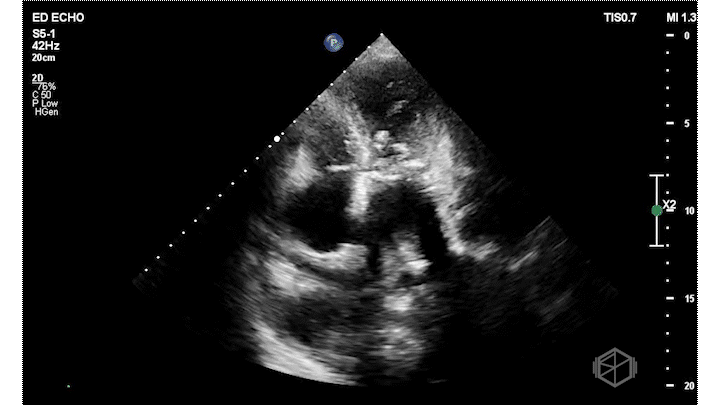

Dr. Frayberg did an echo that showed the following:

The ejection fraction appears grossly normal. There is no pericardial effusion. The right ventricle appears normal size at least in these views. The mitral valve has a very hyperechoic density: severe mitral annular calcification (MAC). There is also a pleural effusion. The patient was admitted for heart failure and acute hypoxic respiratory failure.

Diagnosis: Severe MAC, HFpEF